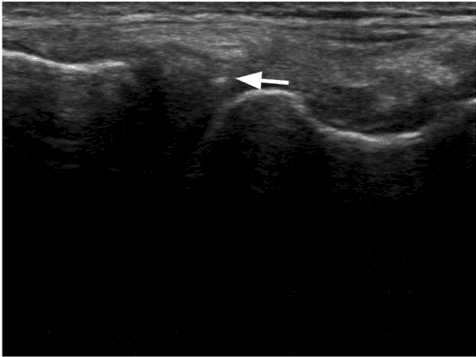

A pilot study to evaluate micro-fragmented adipose tissue injection under ultrasound guidance for the treatment of refractory rotator cuff disease in wheelchair users with spinal cord injury

Nathan Hogaboom, Gerard Malanga, Chris Cherian, Trevor Dyson-Hudson, Unknown, 2021